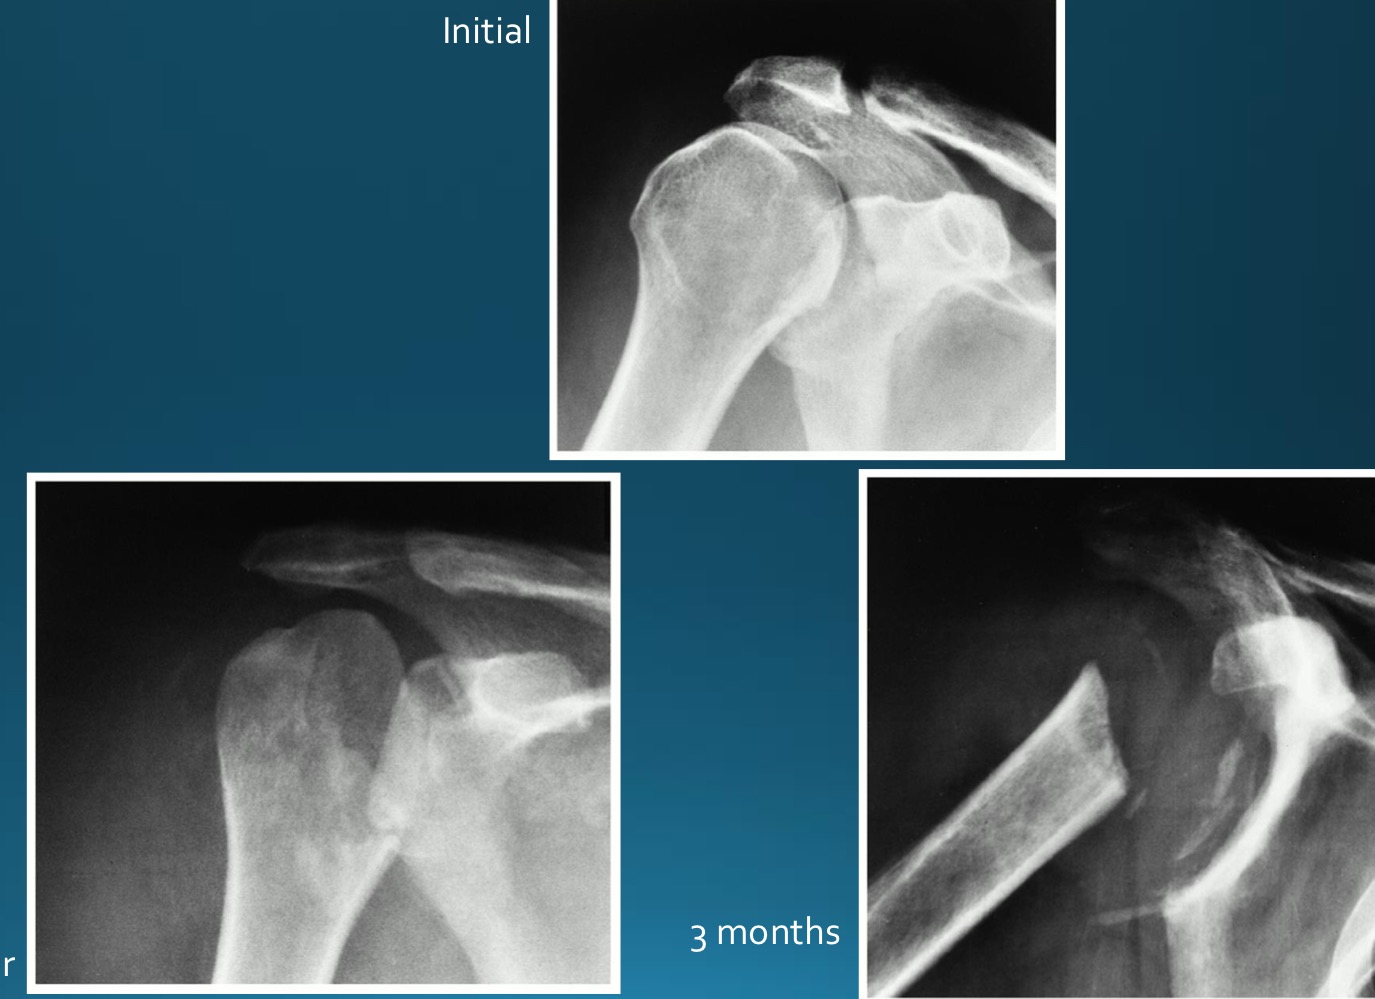

what is the diagnosis?

AS

sacroilitis

what are the signs seen in this image? what diagnosis would you make

rosary bead appearance (wavy appearance in SI joint area)

star sign (at superior angle of SI joint)

what are the signs seen in this image? what diagnosis would you make?

ghost joint (line in SI joint area but no space)